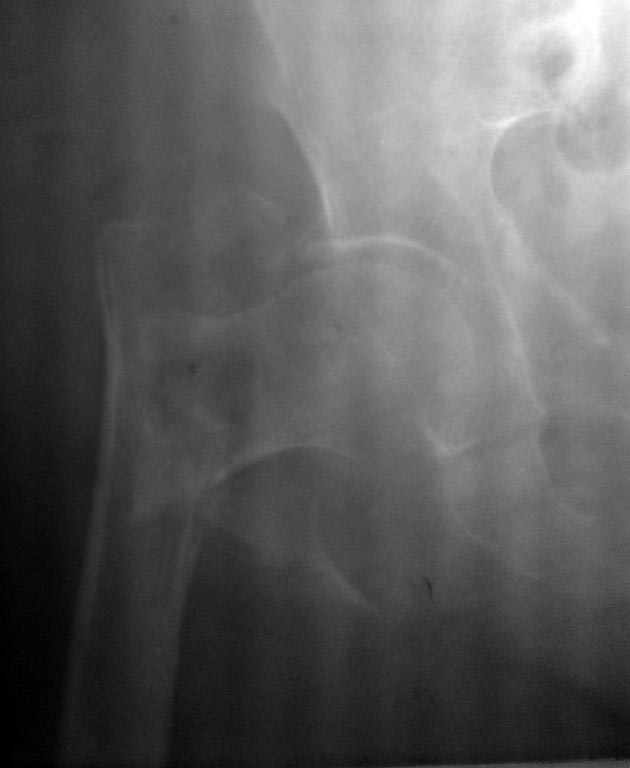

пример перелома, который можно сравнить с Вашим.

Отправитель: Савранский Александр 02 Июнь 2016, 01:58

вид после, нагрузка с 3 дня

Странное какое-то "после"

Отправитель: Андрей 03 Июнь 2016, 00:46

Забыли навигацию снять со стержня и цапки после операции!!!

Снимок похож на интраоперационный, исходя из чего можно предположить, что оперировали без ЭОП.

Коллеги, я дико извиняюсь, но зачем тролить Савранского за представленный интраоперационный снимок? ,получилось кстати неплохо)))

Не стыдно! Все же понимают что мы по доброму шутим!!! Ничего здесь нет такого предосудительного! Всё там хорошо, молодец, особенно если на боковой проекции винт где нужно.

Ну если снимок как образец представляешь, то мог бы винт докрутить в головку то, не идеально имхо

Пока был на конференции- сколько комментов. Спасибо коллегам за специфический ортопедический сарказм, а Лубенцу Александру за поддержку. Снимки действительно интраоперационные, выложил что было под рукой, в телефоне. Оперирую без ЭОПа. По поводу пациентки не переживайте- давно ходит. Интересно все же, что получилось у топикстартера. Всем хорошего настроения!